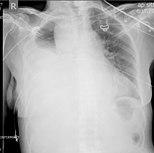

Chest X-ray

Two chest X-rays: left showing a massive left-sided hemothorax; right showing a massive right hemothorax

A chest X-ray is the most common technique used to diagnosis a hemothorax.[23] X-rays should ideally be taken in an upright position (an erect chest X-ray), but may be performed with the person lying on their back (supine) if an erect chest X-ray is not feasible. On an erect chest X-ray, a hemothorax is suggested by blunting of the costophrenic angle or partial or complete opacification of the affected half of the thorax. On a supine film the blood tends to layer in the pleural space, but can be appreciated as a haziness of one half of the thorax relative to the other.[5] A small hemothorax may be missed on a chest X-ray as several hundred milliliters of blood can be hidden by the diaphragm and abdominal viscera on an erect film. Supine X-rays are even less sensitive and as much as one liter of blood can be missed on a supine film.[24]